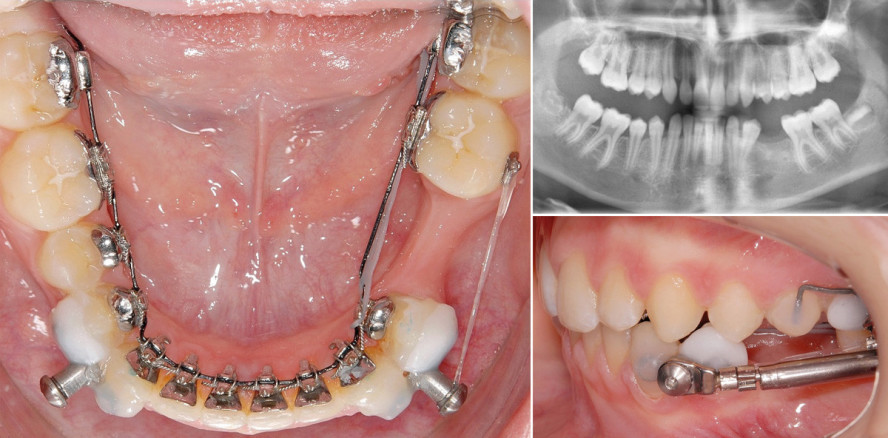

Anhand eines Patientenbeispiels, bei dem die ersten OK-Molaren und ersten UK-Prämolaren extrahiert wurden, zeigt Dr. Gianluigi Fiorillo den...

Anhand eines Patientenbeispiels, bei dem die ersten OK-Molaren und ersten UK-Prämolaren extrahiert...